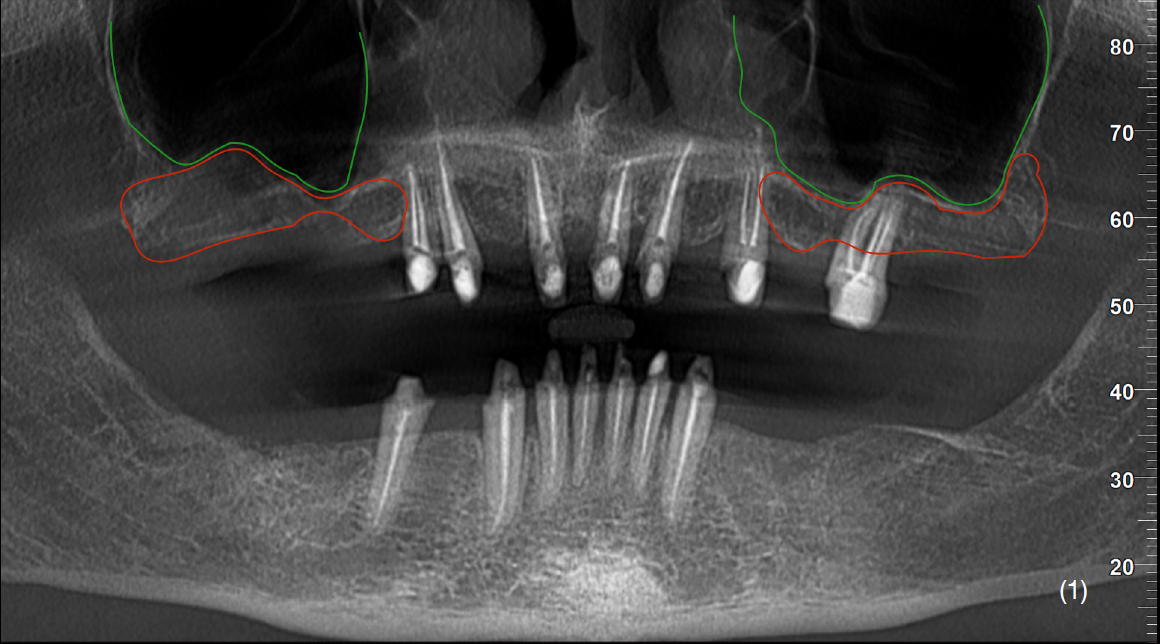

Первинна ситуація

67-річний пацієнт, без шкідливих звичок, з незадовільним пародонтальним статусом та підвищеним рівнем глюкози звернувся в клініку для заміни старих нефункціональних ортопедичних конструкцій на верхній та нижній щелепах.

В пацієнта також були скарги на кровоточивість ясен, гноєтечу, неприємний запах, рухомість конструкцій, незадовільний естетичний вигляд.

В анамнезі зазначалося, що тотальне ортопедичне лікування було проведене 10 років назад.

На етапі планування було прийнято рішення про збереження зубів верхньої щелепи та подальшого використання їх, як опори під незнімні конструкції, з додатковим встановленням імплантатів в ділянках дефектів.

Також було звернено увагу на недостатню вертикальну кісткову пропозицію в дистальних відділах 1 та 2 квадрантів. Зуби нижньої щелепи було заплановано видалити з огляду на недостатню кісткову підтримку та неможливість протезування.

Після детального вивчення даних комп’ютерної томографії пацієнта, було затверджено план лікування, який складався із двох хірургічних етапів.